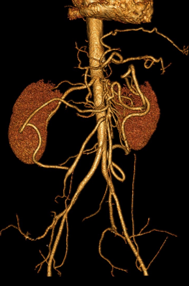

Digestif DES BASE

L’essentiel sur l’ischémie intestinale aiguë en imagerie

DANSE E. - UCL

Année académique 2020-2021